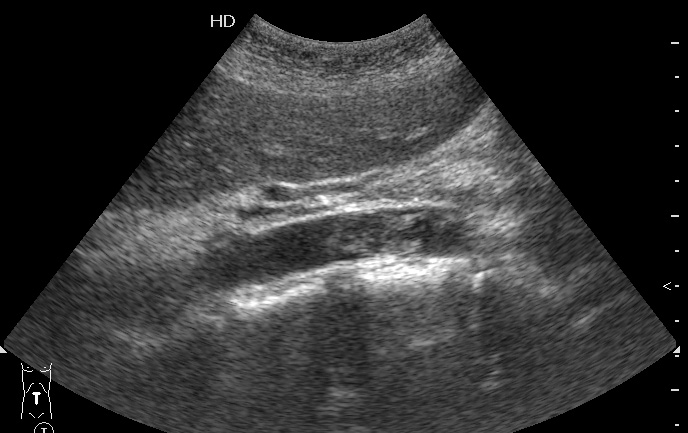

Пожилая женщина, поступила в БСМП с резкими болями в ногах. Пульс на бедренных артериях отсутствует.

Продольный скан аорты

Назначено консервативное лечение, назавтра появился кровоток в бедренных артериях.